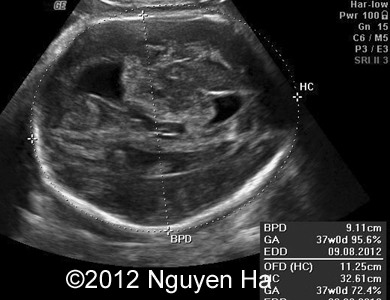

A 30-year-old woman (G1P0), with unremarkable family history, presented to our unit at 36 weeks of her pregnancy. She did not undergo any previous screening tests. Our examination (and repeated scan after four days) revealed following findings:

Figures 1-7: 36 wekks of pregnancy.

A 30-year-old woman (G1P0), with unremarkable family history, presented to our unit at 36 weeks of her pregnancy. She did not undergo any previous screening tests. Our examination revealed unilateral hypoechoic inhomogeneous mass within cerebral parenchyma. Our initial diagnosis was teratoma, but repeated exam after four days showed structural changes and different echogenicity of the mass and so our final diagnosis was cerebral hemorrhage. The findings were confirmed by MRI scan.

Figure 1-7: 36 wekks of pregnancy.

Figure 8-15: 4 days later; image 1-4 suggesting a middle cerebral artery infarction with formation of schizencephaly, no more cortex at the level of the insula.